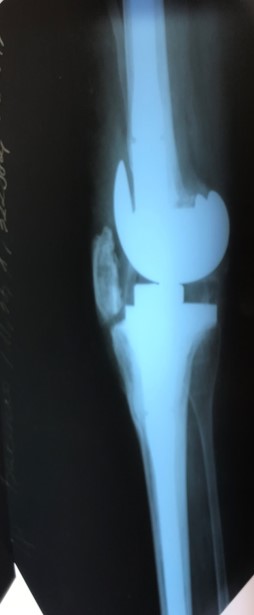

Приклад 3. Хвора К. 52 років. Діагноз: Деформівний IVст. гонартроз, стан після ТЕП лівого КС (2013р.). ІМТ хворої складає 35 балів. Асептична нестабільність компонентів ендопротеза лівого колінного суглоба, міграція великогомілкового компоненту (2017 р.) (рис. 2 а). Хворій виконано ревізійне ендопротезування: видалення компонентів ендопротезу, виявлений дефект медіального виростку великогомілкової кістки тип Т3А за класифікацією АОRI [G.A. Engh, C.H. Rorabeck, 1997]. Під час операції виконана кісткова пластика дефекту. Використаний ендопротез колінного суглоба з подовжувачами.

Проектування та виготовлення індивідуальних аугментів для заміщення  дефектів суглобів: М, 48р, асептична нестабільність онкологічного ендопротеза . Заміщення дефекту індивідуальним аугментом та ревізійним ендопротезом , фіксація БІС, ПММА